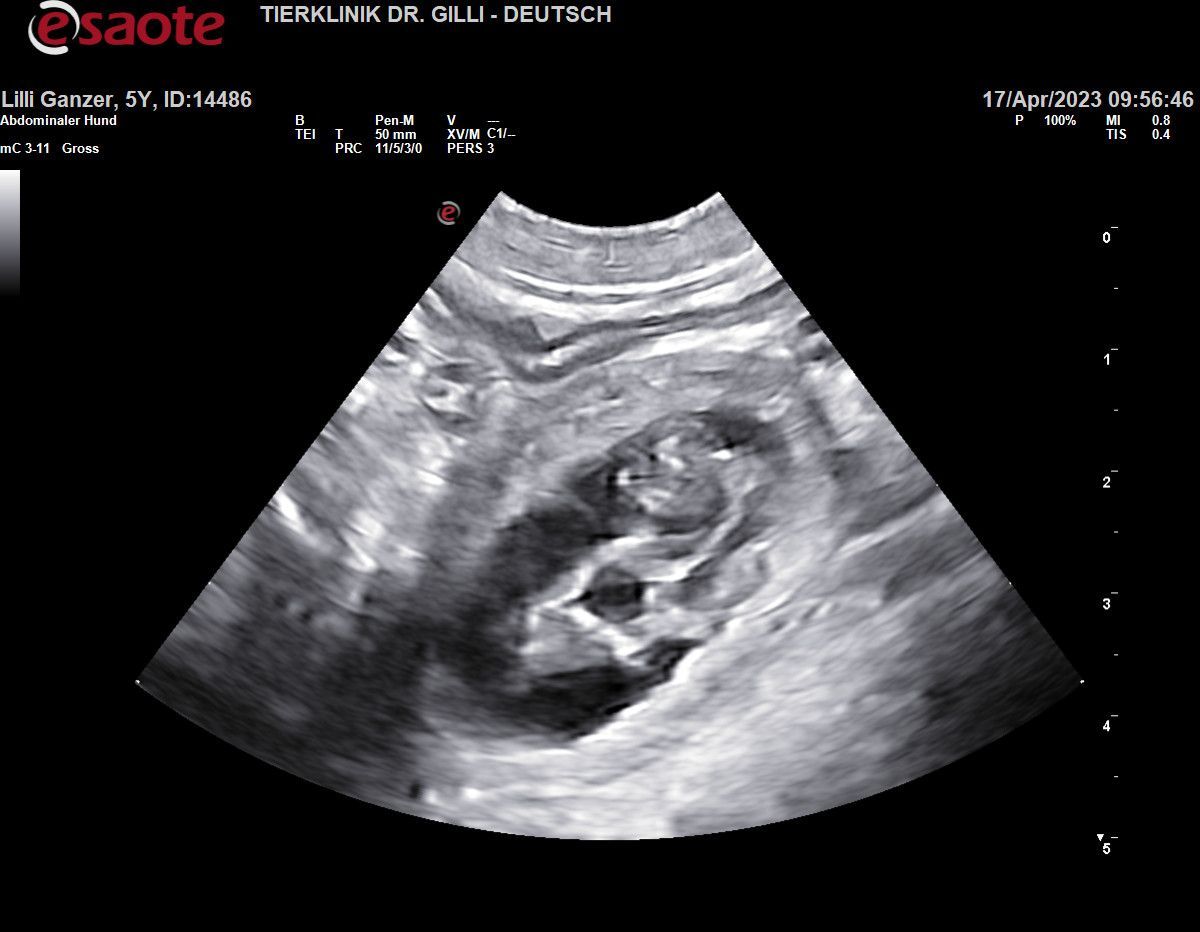

Heute Nacht, 20.05.2023, war es nun endlich soweit!!!

ab 2:50 Morgens bis 5:22 brachte unsere Lilli Fee, 5 bildhübsche Babys zur Welt!!!

Mama & den Babys geht es ausgezeichnet. es war eine Bilderbuch Geburt

es sind 3 Buben und 2 Mädchen

wir werden jeden Einzelnen, in den nächsten Tagen vorstellen